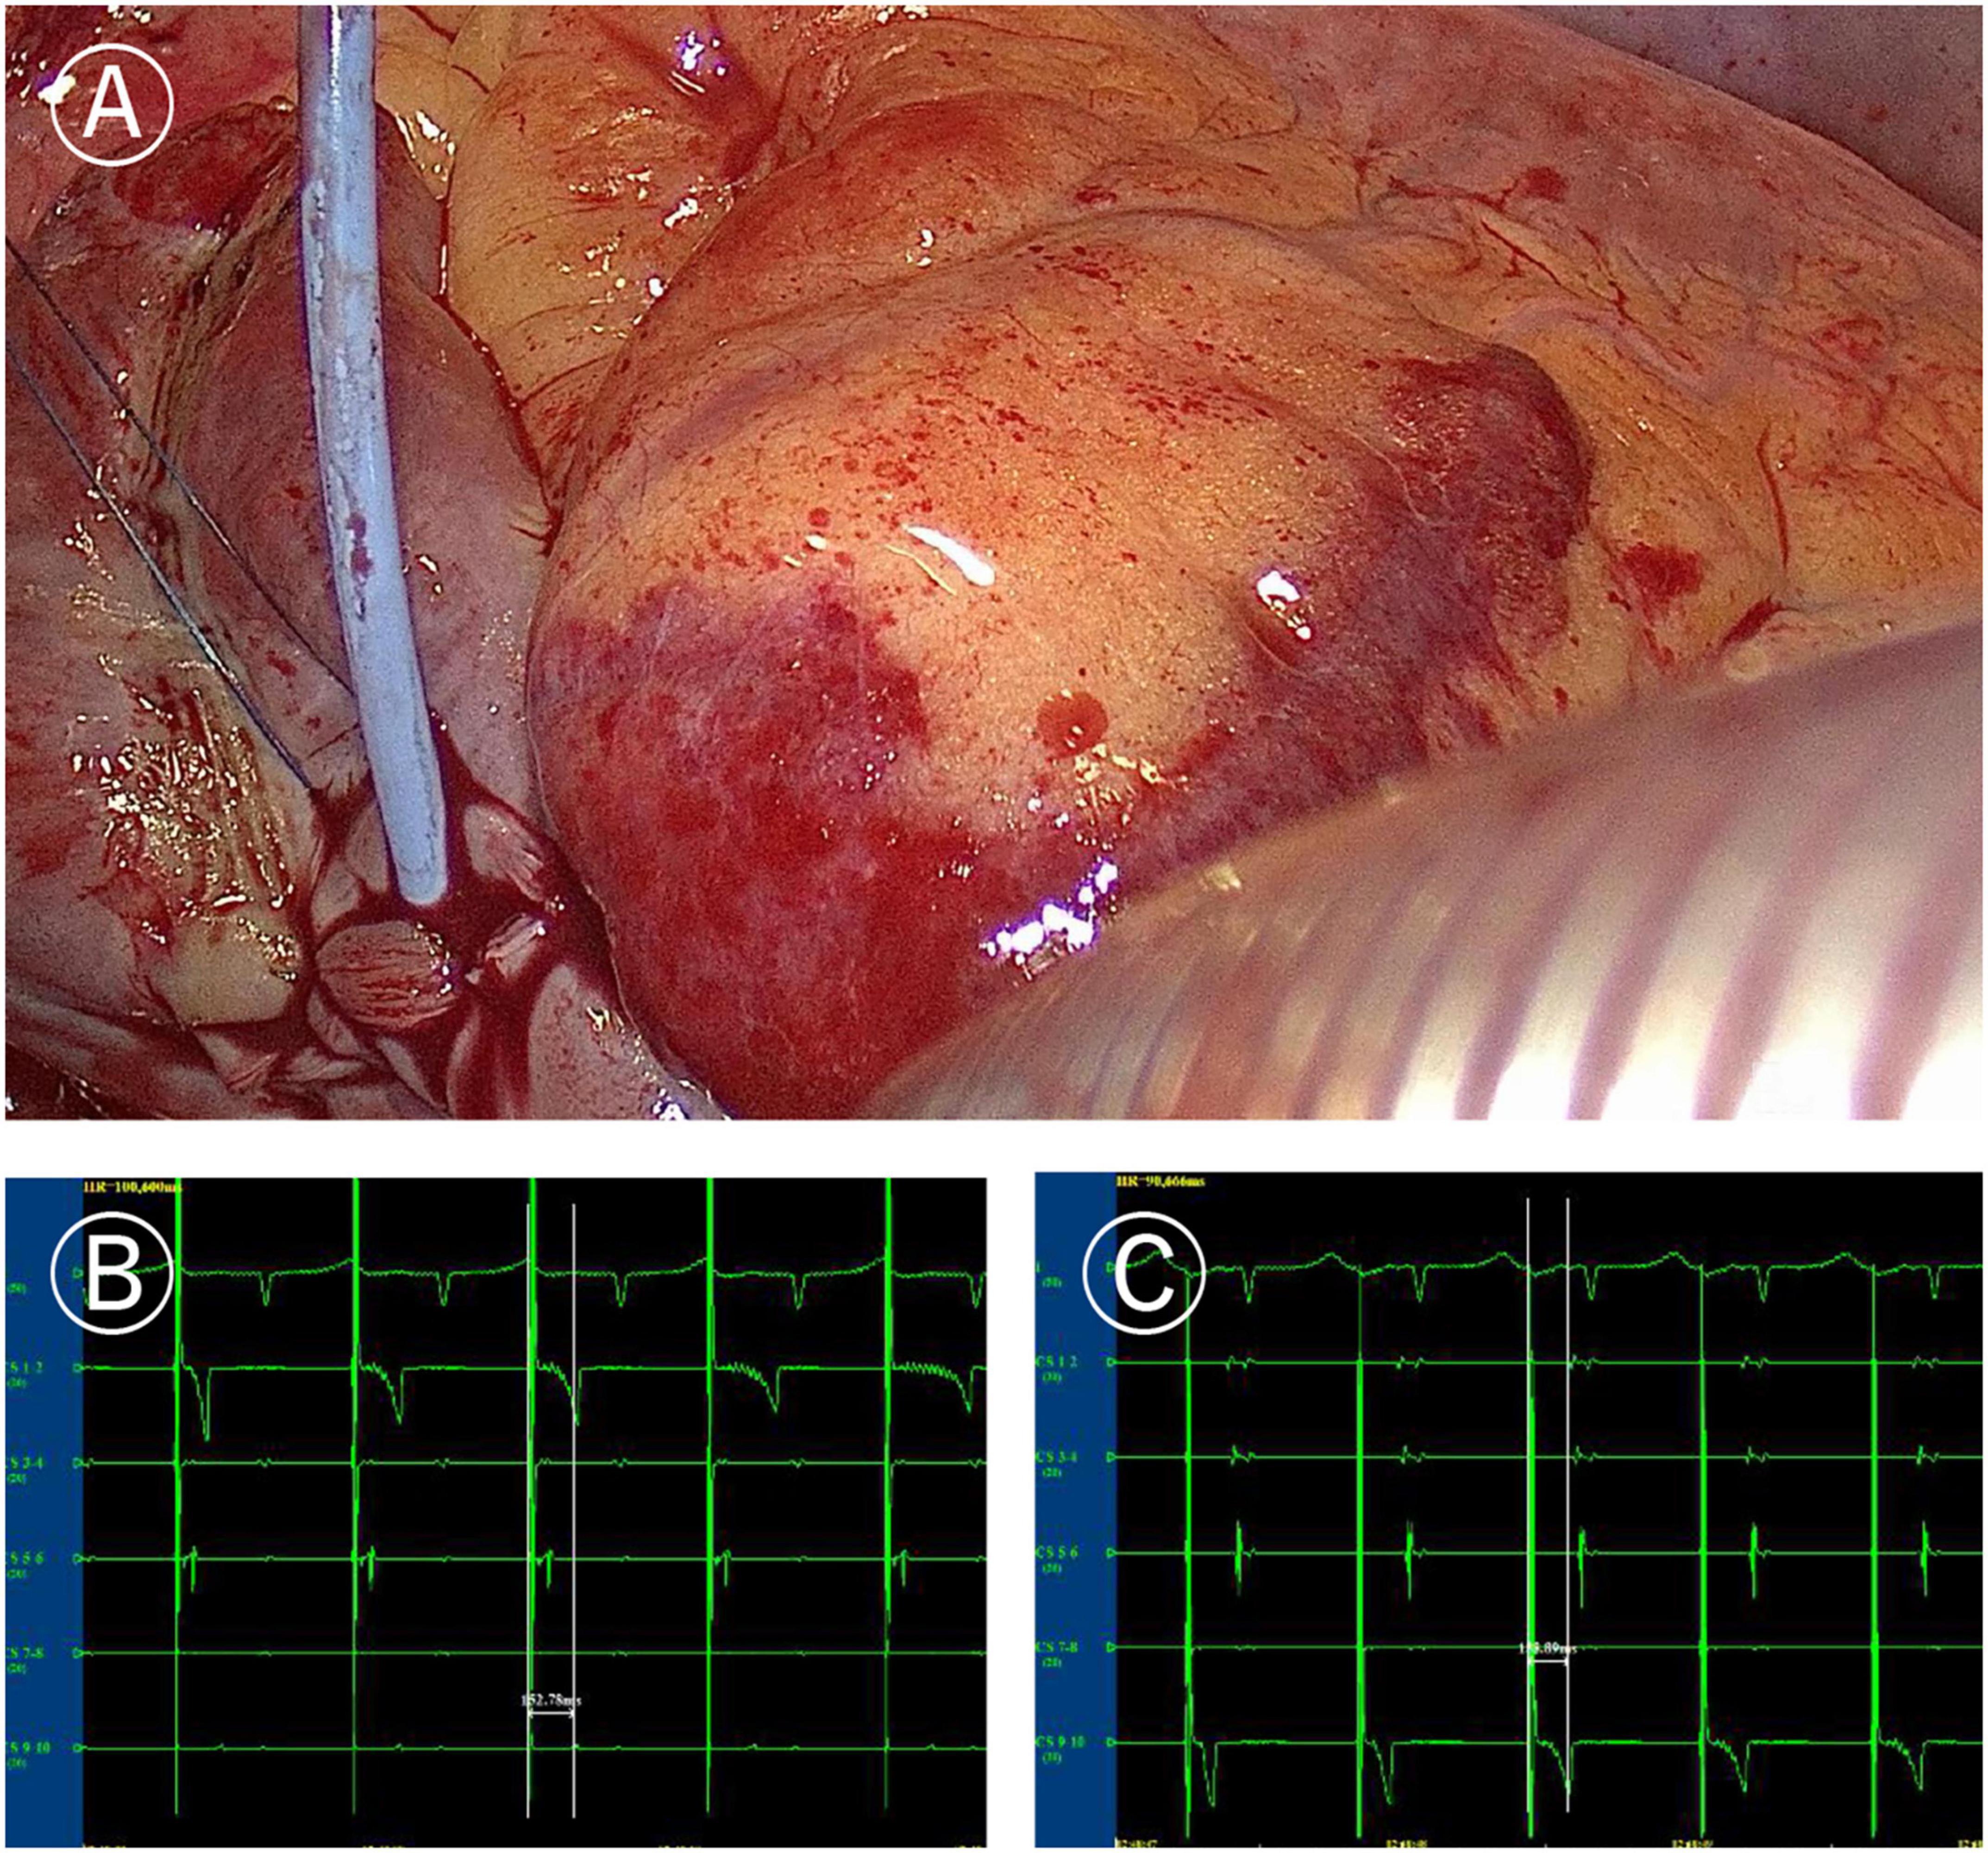

In the Electrophysio-Maze group, all patients underwent AF induction before and after the Cox-Maze IV procedure (Figure 1). The induction was performed with cannulization but without cardiopulmonary bypass, making the conditions consistent as much as possible. AF was induced in 88.1% (37/42) of all patients before Cox-Maze IV and was induced in 14.3% (6/42) of all patients after the Cox-Maze IV procedure. The bidirectional electrical isolation of the mitral annular isthmus ablation line (Figure 2), “box” ablation lines (Figure 3), and tricuspid annular ablation line (Figure 4) was successfully mapped in each patient. The rate of incomplete bidirectional electrical isolation of “box” ablation lines immediately after Cox-Maze IV was zero (the rate of complete bidirectional conduction block of “box” ablation lines immediately after Cox-Maze IV was 100%), and the rate of incomplete bidirectional electrical isolation of mitral isthmus ablation lines or tricuspid annulus ablation lines was 23.8% (10/42), wherein the rate of incomplete bidirectional electrical isolation of both mitral isthmus and tricuspid annulus ablation line was 7.14% (3/42), the rate of incomplete bi-directional electrical isolation of single mitral isthmus ablation line was 7.14% (3/42), and the rate of incomplete bidirectional electrical isolation of single tricuspid annulus ablation line was 9.52% (4/42). In two cases of incomplete bidirectional electrical isolation in single tricuspid annulus ablation line, complementary ablation was performed, and then electrophysiological mapping was performed again to ensure that the subsequent electrophysiological mapping confirmed the final complete bidirectional electrical isolation. The final incomplete bidirectional electrical isolation rate of mitral isthmus or tricuspid annulus ablation line was 19.0% (8/42). The incomplete bidirectional electrical isolation rate of ablation lines was correlated with AF inducibility immediately after Cox-Maze IV procedure but not with AF inducibility before Cox-Maze IV (Table 3).

Figure 2. Ablation line mapping of mitral isthmus. (A) Coronary sinus catheter mapping of mitral isthmus ablation line. (B) Distal (CS1-2) delay during proximal (CS9-10) pacing of coronary sinus catheter (more than 120 ms). (C) Proximal delay during distal pacing of coronary sinus catheter (more than 120 ms).